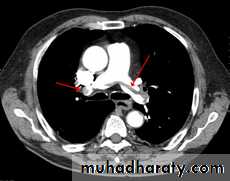

• CXR oligemia or linear or triangular consolidation,

• Pulmonary angiograms: filling defects or obstruction of pulmonary arterial branches.